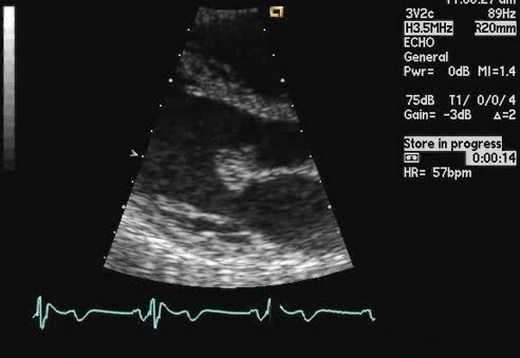

Трансторакальная и чреспищеводная эхокардиография для выявления причины эмболии

Чувствительность трансторакальной эхокардиографии (TTЭхоКГ) для обнаружения потенциальных источников эмбола низкая, так как наиболее частые потенциальные причины плохо визуализируются с помощью этой методики. При отсутствии клинических сердечных заболеваний диагностическая ценность составляет всего 1%, а с клиническими сердечными аномалиями увеличивается до 15%. Его основное применение - оценка глобальной и региональной систолической функции ЛЖ и апикального тромба в левом желудочке.

Оценка межпредсердной перегородки и грудной аорты. В целом чреспищеводная эхокардиография (ЧПЭХоКГ) выявляет значительно больше потенциальных источников эмболии, чем TТЭхоКГ (39-57% против 15-19%). Оценка потенциального источника эмбола в настоящее время является основным клиническим показанием для ЧПЭХоКГ в большинстве лечебных учреждений (26%). Использование контраста могло бы повысить эффективность ЧПЭхоКГ для обнаружения тромбов в ушке левого предсердия, и польза была максимальной, когда исследования были ограничены наличием спонтанного эхо-контрастирования или когда была низкая скорость опорожнения ушка левого предсердия. Кроме того, контраст часто помогает отличить плотный спонтанный эхоконтрастный осадок и необходим для оптимальной визуализации ЛП и тромба, в частности, расположенной сзади ушка левого предсердия (наиболее частое место расположения тромба). Однако, вероятно, лучше рассматривать эти два метода как взаимодополняющие, а не исключающие друг друга.